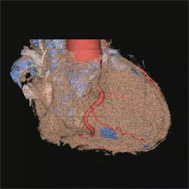

冠動脈CT

CT画像を用いた3次元画像は今でこそ多くの施設で活用されるようになりましたが、その開発に当放射線科は深く関ってきました。現在では、大動脈瘤や大動脈解離などの大血管疾患や閉塞性動脈硬化症などの末梢血管疾患に加え心臓の冠動脈の3次元画像も提供できるようになり、これまで血管造影でしか得られなかった情報をおよそ10分程度の外来検査で正確に知ることができるようになりました。また、早期脳梗塞の診断において注目されているCT perfusion(CT灌流画像)も海外の大学と共同で開発し国内外での普及に努めてきました。これらの成果は欧州放射線学会から金賞ならびに銀賞を授与され、また日本医学放射線学会でも金賞を受賞し、広く国内外で認められています。